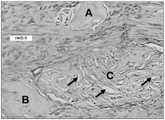

Fig. 7 is a photograph showing the results of collagen staining with alcian blue in theparavertebral space 5 weeks after collagen injection. Three amorphous homogeneous collagen islands were surrounded by scar tissue. Island a showed no cell infiltration and island B showed very limited cell infiltration. Island C showed a high degree of fibroblast infiltration. Cells appear to reorganize the tissue as indicated by the reabsorbing regions (black arrows) in the collagen tissue. There was no evidence of inflammatory reaction.